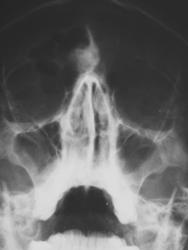

Иллюстрации 1, 2. На цифровой флюорограмме придаточных полостей носа, произведенной в прямой стандартной проекции в носо-подбородочном положении, в лобной пазухе, больше справа определяется тень значительной интенсивности, с довольно ровными, четкими контурами, однородной структуры. Интерпретация данной тени сложности не вызвала, так как по своим скиалогическим характеристикам представляет типичную остеому, а с учетом «излюбленной» локализации, дифференциально – диагностических трудностей не возникло.

Определяется снижение прозрачности в правой гайморовой полости базально и больше латерально средней интенсивности, однородной структуры, с четкой выгнутой границей, что по своим скиалогическим характеристикам свидетельствует о кистозном образовании.

При анализе иллюстраций 3, 4, 5, 6 чётко дифференцируется неоднородность тени остеомы за счет очаговых уплотнений.

На иллюстрациях 7 и 8 представлена теневая картина правой гайморовой полости «с увеличением изображения».